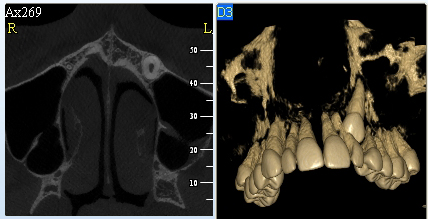

NewTom Giano

Jedná se o nejnovějším přístroj ze skupiny dentálních hybridních CBCT (3D) + 2D (pan i ceph) systémů. Opět umožňuje na základě jediného snímkování vytvořit všechny typy RTG zobrazení, které jsou pro lékaře potřebné. Používaná technologii tzv. „kuželového paprsku“ a speciální senzory pro minimální zátěž při snímkování pacienta.

Vyšetření pomocí tohoto přístroje (nebo

3D DVT - NewTom) a získaná data používáme

pro každou implantaci, dále ve stomatochirurgii (zlomeniny čelistí, zuby moudrosti, cysty, onemocnění čelistního kloubu), ortodoncii (retinované zuby, nadpočetné zuby), parodontologii atd.